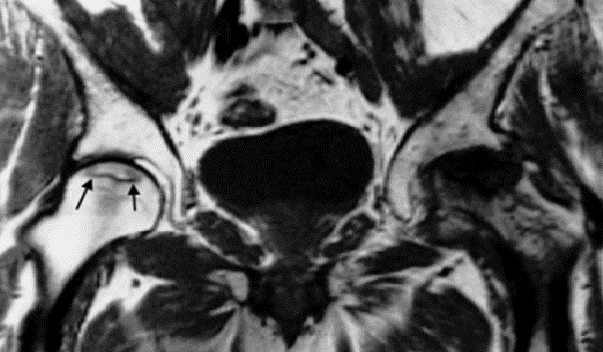

Cervical disk herniation

MRI cervical spine (T2-weighted; sagittal plane) of a

patient with symptoms of cervical myelopathy

A herniated disk at C5–6 effaces the dural sac and compresses the spinal cord. Hyperintense compression-induced edema is seen within the cord